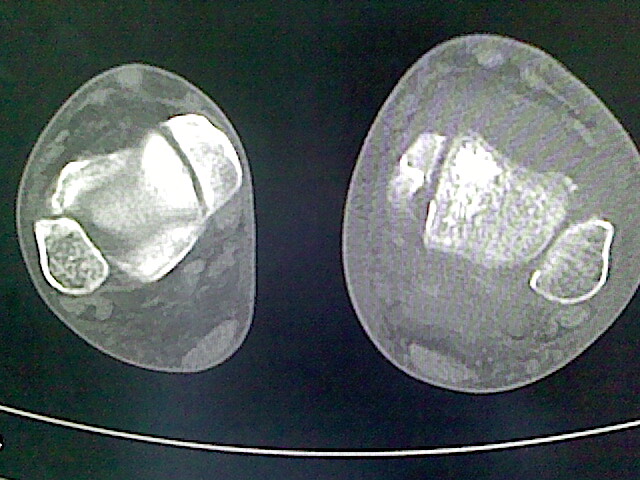

标题: CT16814:男,76岁,左小腿疼痛,不能站立 大家给看看 [打印本页]

男,76岁,左小腿疼痛,不能站立

本例骨质改变主要表现为滑膜或韧带区的骨侵蚀融解(胫腓联合区骨质破坏无硬化边),距骨后部骨质破坏区有硬化边及死骨样改变.所以,本例考虑关节结核可能性大,绒毛膜结节性滑膜炎多发于中年,且极少见于膝髋以外的关节,骨质硬坏也以压陷吸收为主,有明显的硬化边,骨膜增生呈结节状(可以mr鉴别),所以本例暂除外.

另不除外可引起相似表现的其他炎症如布氏杆菌性关节炎等